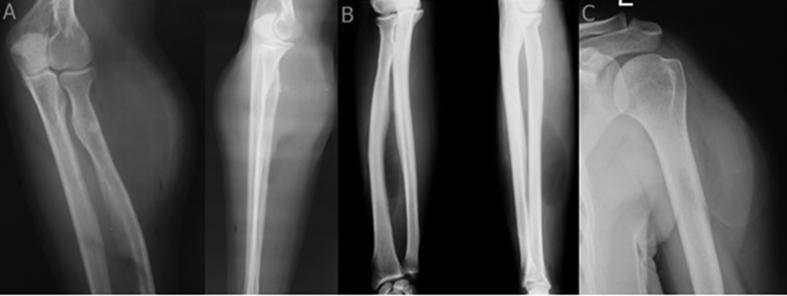

Of the 12 lipomas, 5 were localized in the proximal arm, 4 in the forearm, 1 in the distal arm, 1 in the distal thigh and 1 in the distal tibia. All patients presented with a progressive, slow-growing mass that was associated with thumb extension weakness in 1 case, and brachialgia-like symptoms in 1 case. Plain radiographs showed a juxtacortical mass in all cases and irregular ossification in 3 cases. In all cases, marginal excision was performed and no clinical recurrence was observed after a mean follow-up of 16 months.

结果

12例脂肪瘤中,5例位于上臂近端,4例位于前臂,1例位于上臂远端,1例位于大腿远端,1例位于胫骨远端。所有患者均表现为进行性生长缓慢的肿块,其中1例伴有拇指伸展无力,1例出现臂痛样症状。X线平片显示所有病例均有皮质旁肿块,3例有不规则骨化。所有病例均行边缘切除术,平均随访16个月后未观察到临床复发。

Parosteal lipomas are uncommon tumors that can be diagnosed with their characteristic radiological features. Parosteal lipomas occurring in the proximal radius may easily cause paralysis of the posterior interosseous nerve or muscle weakness.

结论

骨旁脂肪瘤是罕见肿瘤,可通过其特征性影像学表现进行诊断。发生于桡骨近端的骨旁脂肪瘤可能易导致骨间后神经麻痹或肌肉无力。